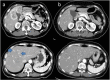

A 62-year-old woman diagnosed with gallbladder cancer exhibiting broad liver invasion and metastasis to Couinaud's hepatic segments 4 and 8 (S4 and S8) consulted her regular doctor. Owing to the presence of liver metastases, she received treatment with gemcitabine plus S-1. After four cycles of chemotherapy, the size of the main lesion dramatically decreased and the two liver metastases disappeared. After six cycles of chemotherapy, the patient was referred to our hospital for surgical treatment. Upon admission, there was no evidence of any distant metastasis, based on a detailed radiological examination. Therefore, we performed cholecystectomy and central bisegmentectomy of the liver after obtaining the patient's informed consent. Pathological examination demonstrated viable cancer cells with granuloma formation and calcification in the gallbladder, as well as regenerative changes without viable cancer cells in S4 and S8 of the liver. Gemcitabine plus S-1 was again administered as postoperative adjuvant chemotherapy. One and a half years after the surgery, there were no signs of recurrence. In patients selected according to their response to chemotherapy, surgical treatment might therefore be effective against gallbladder cancer with metastasis.